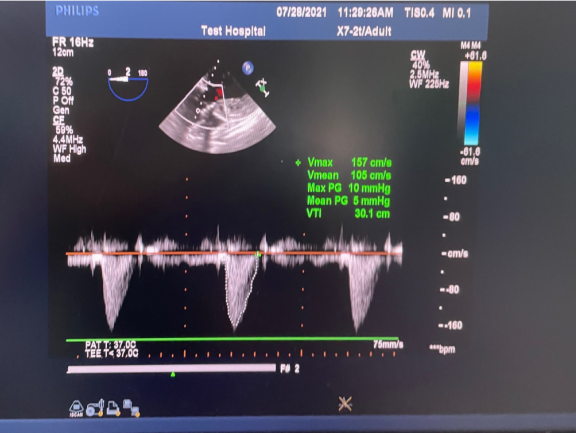

手术采用经心尖入路的策略。患者全麻后,在左侧心尖处(胸部对应位置)切开3-4cm的小切口,随即在DSA及超声引导下植入Ken-Valve瓣膜,手术仅耗时6分钟。术后即刻返流由术前大量转为消失,术后测得跨瓣压差为6mmHg,血流速度为1.2m/s。

术后超声影像图